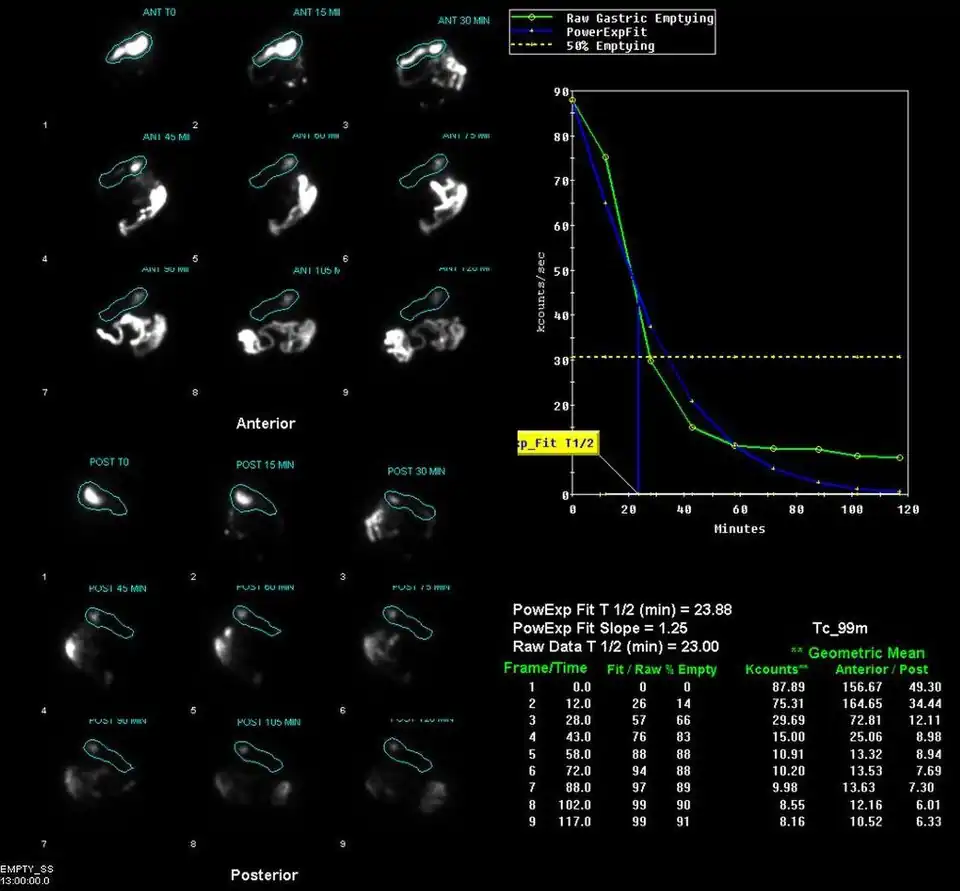

Example gastric emptying images

A gastric emptying study is a nuclear medicine study which provides an assessment of the stomach's ability to empty. It may be used if there are complications after gastric surgery, for gastric reflux, or suspected gastroparesis amongst other indications.[1] Scintigraphy that uses gamma cameras to create two-dimensional images is generally regarded as the gold standard for gastric emptying.[2][3]

Having fasted for around four hours before the study, the patient is given a solid or semi-solid meal, such as scrambled eggs on toast or porridge, which has been prepared with a radiopharmaceutical component. Typically technetium-99m sulphur colloid or DTPA is used.[4][1][5] Some studies may also involve a liquid component, which is labelled with indium-111 DTPA.[5] Images are acquired with a gamma camera, initially dynamically and then at intervals for up to 2-3 hours.[1][5][6]

The stomach time-activity curve is produced from geometric mean of anterior and posterior imaging. Half-emptying time, the lag-phase duration for solid studies, and percentage of food left at various time points are calculated.[7]